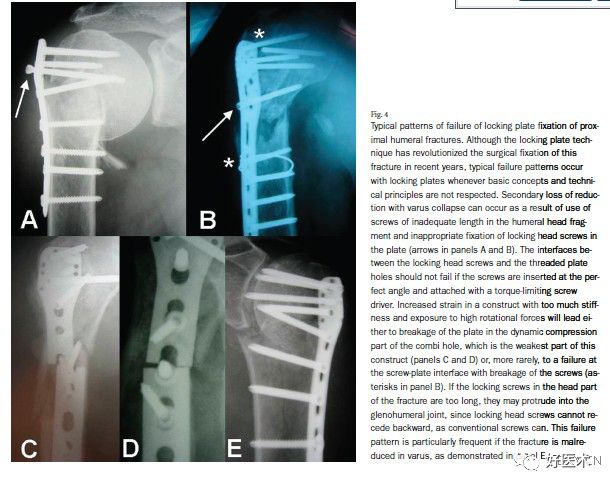

图片

动力加压孔是联合锁定钢板上最薄弱的部位。术中钢板塑形时,折弯就发生在这里;当局部应力集中增加或张力增加时,钢板断裂也发生在此。因此,当使用桥接钢板固定粉碎骨折时,至少要在骨折线周围空出3-4个螺钉孔已获得一较大的应力分散区。

传统钢板的断裂发生在螺钉-钢板界面而导致螺钉头断裂;与之相比,锁定钢板的螺钉-钢板锁定螺孔界面是其最坚固的部分。锁定螺钉头与螺钉杆之间的直径差异较之普通螺钉要小很多,所以在此断裂的可能性也相应变小。

然而锁定螺钉头在骨折长期不稳定以及旋转力导致的张力作用下也可发生断裂。正如图所示肱骨近端不愈合导致的断裂一样。